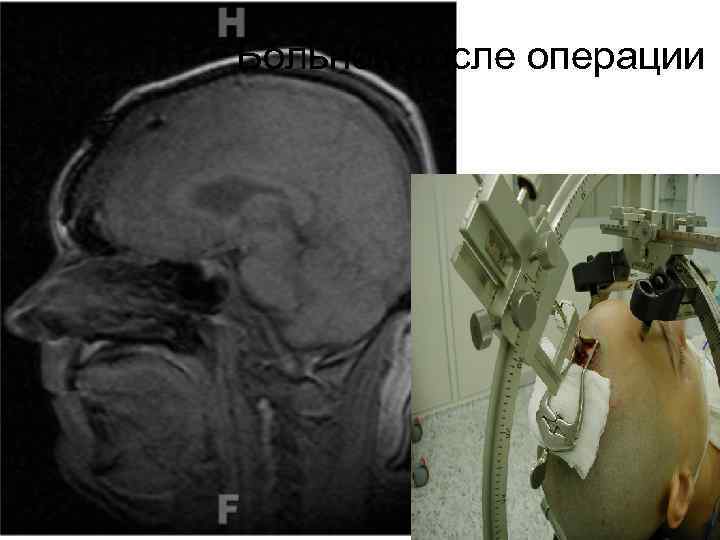

Больной после операции 66

67